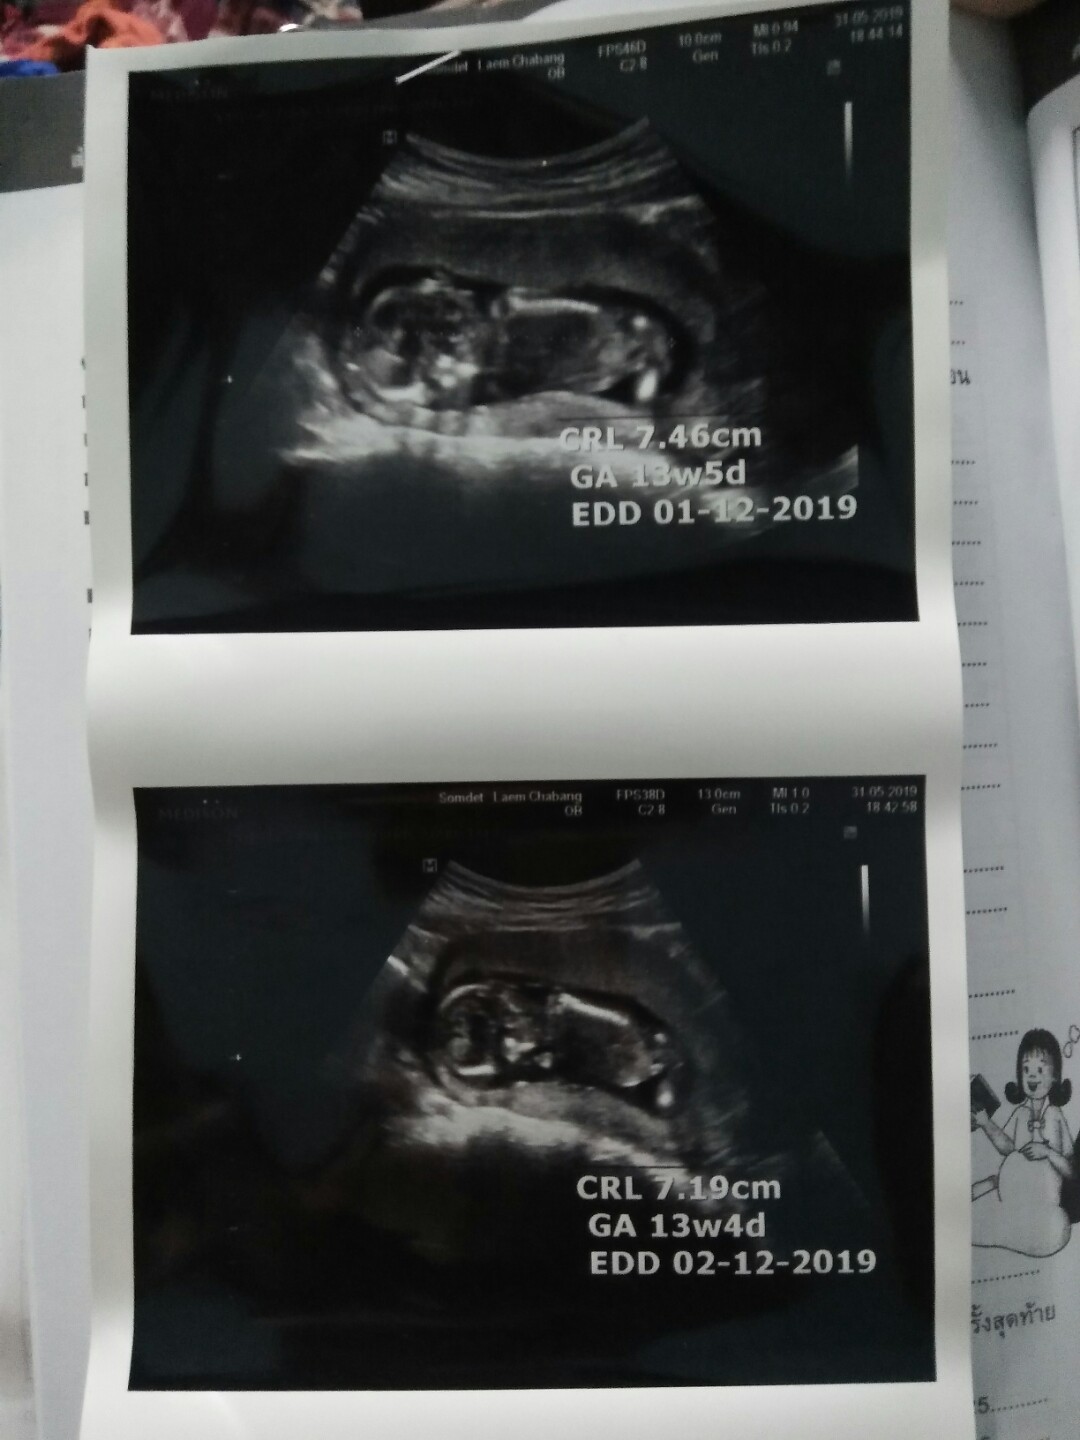

13w5d ค่ะ ตอนนี้ 16w1d